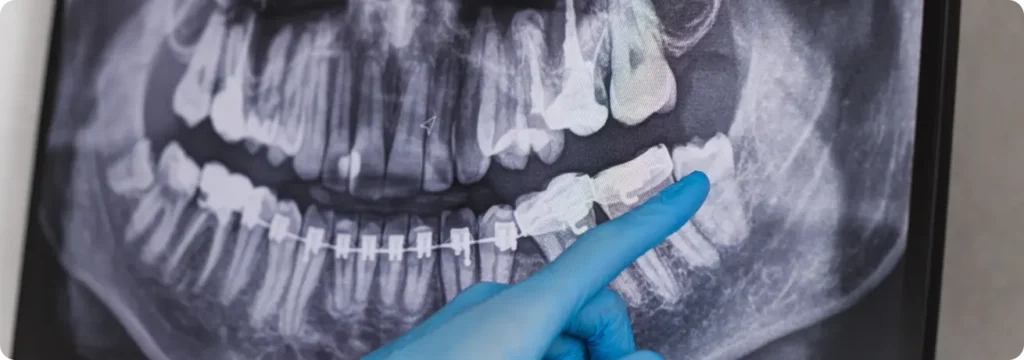

From complex tooth extractions to reconstructive jaw surgery, every procedure is performed with surgical precision and patient comfort as the top priority.

Oral surgery becomes necessary when pain, infection, or dental problems start interfering with your daily life. From wisdom teeth removal to jaw alignment or treating facial injuries, surgery offers lasting relief. Our focus is precise care, helping you heal comfortably and regain confidence with every step.